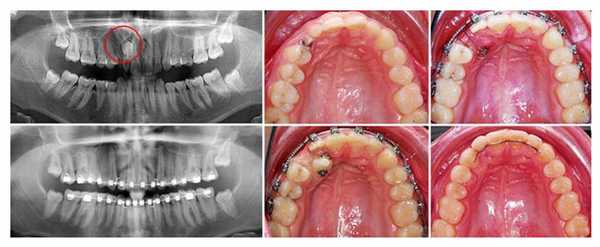

Ортодонтическое лечение

При отсутствии прямых показаний для удаления ретинированного зуба и наличии для него свободного места в зубном ряду первым этапом проводится хирургическое лечение - иссечение десны или части кости, а затем ортодонтическое лечение - перемещение зуба в правильное положение с помощью брекетов или кнопок.

Принципы лечения: можно ли избежать операции

Многие пациенты уверены, что ретинированный дистопированный зуб - это обязательно повод для хирургического вмешательства. Но стоматологи стараются не резать без серьезной на то причины. Поэтому, если ваши лишние зубы не воспалены и не мешают вам жить, вполне можно избежать операции. Еще врач может назначить установку жестких металлических брекетов, которые «вытянут» частично прорезавшийся зуб из тканей десны и впишут в зубной ряд.

Обычно лечение проходит следующим образом:

- Проходит диагностика, которая включает визуальный осмотр и создание панорамного снимка челюсти.

- Врач изучает результаты и принимает решение о том, нужно ли удалять зуб. Если да, то назначается операция.

- Если стоматолог видит другие способы решения проблемы, он предпочитает их. В первую очередь рассматривается установка брекет-системы. Для этого нужно, чтобы в зубном ряду было место, где мог бы разместиться новый элемент.

- Если брекеты не требуются или пока их нельзя поставить, врач пытается помочь зубу прорезаться. Для этого используют медикаменты и хирургическое вмешательство. Помощь в прорезывании часто используется, когда «зуб мудрости» частично остался под десной, но располагается правильно.

Этапы лечения ретинированного зуба